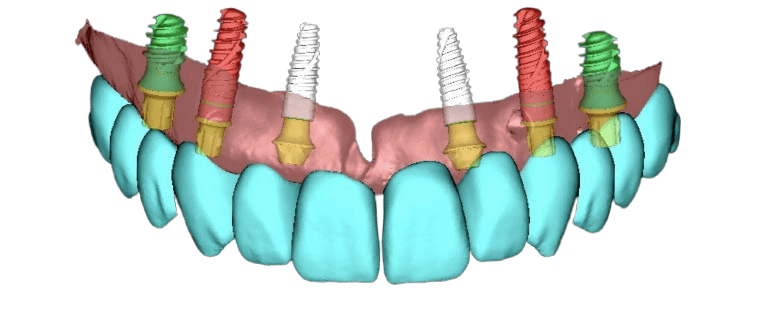

Die periimplantäre Chirurgie befasst sich mit dem Erhalt und der Wiederherstellung von Knochen und Weichgewebe um Implantate herum. In unserer Praxis setzen wir auf prothetisch geführte Planung und Implantation, um eine optimale Positionierung des Implantats – sowohl funktionell als auch ästhetisch – zu gewährleisten.

Vor oder nach der Implantation treten häufig Knochen- und Weichgewebedefizite auf, die horizontale oder vertikale Knochendefekte oder unzureichend festes, keratinisiertes Zahnfleisch sein können. Diese Defizite können die Langzeitstabilität und das ästhetische Ergebnis des Implantats erheblich beeinträchtigen.

Ist eine zahnärztliche Versorgung nach FP1-Standard nicht möglich und kann horizontaler oder vertikaler Knochenverlust nicht ausgeglichen werden, kommen alternative Methoden zum Einsatz. Bei mäßigem Knochenverlust und massivem Weichgewebsverlust – oder wenn der Patient aus Zeitgründen, finanziellen Erwägungen oder aufgrund von Angst keine Knochen- und Weichgewebsaugmentation wünscht – stellt die Versorgung nach FP2-Standard die ideale Lösung dar. Hierbei wird rosafarbene Keramik verwendet, die das fehlende Weichgewebe ästhetisch ersetzt und gleichzeitig ein stabiles und dauerhaftes Ergebnis gewährleistet.

Bei einem größeren Knochen- und Weichteildefekt ersetzen wir im Rahmen des festsitzenden Zahnersatzes 3 sowohl den Knochen als auch das Zahnfleisch durch die Zahnprothese (entweder Zirkon- oder Kunststoffprothesen - mit individuell ausgewählten Zähnen aus einem hochwertigen Premium-Set und einer Zahnfleischimitation, zum Beispiel aus Gradia-Material).